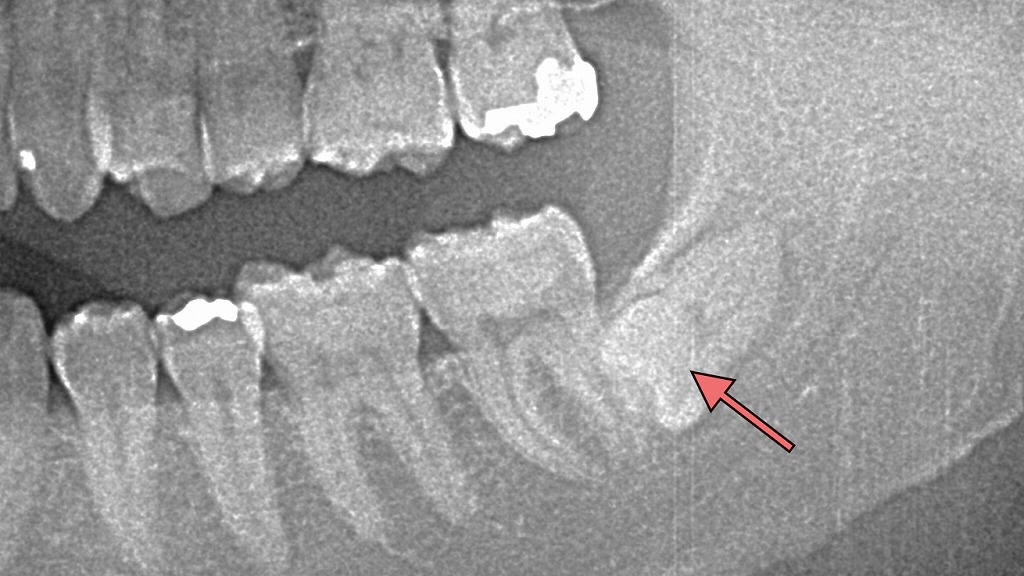

親知らずが埋伏歯となったレントゲン画像

この画像は、下顎のパノラマレントゲン画像です。

赤い矢印で示された部分には、下顎の親知らず(第三大臼歯)が確認されます。

この親知らずは骨の中に完全に埋まっており、典型的な埋伏智歯(まいふくちし)の状態です。

🦷 観察ポイント

- 矢印先の歯は、**下顎骨の内部に横向き(水平)**に位置しています。

- 手前の第二大臼歯の歯根に歯冠の先端が接触しており、圧力がかかっている状態です。

- 埋伏歯は下方にあり、**下歯槽管(神経や血管の通る管)**に近接している可能性があります。

⚠️ この状態で起こりやすいトラブル

- 智歯周囲炎(ちししゅういえん)

歯ぐきの腫れ・痛み・口が開けにくいなどの症状が出る。 - 隣の歯(第二大臼歯)の虫歯や歯根吸収

埋伏歯が接触することで清掃が難しく、虫歯・歯周病の原因となる。 - 抜歯が難しくなる

神経との距離が近いと、抜歯時に神経損傷のリスクが上がる。

🩺 治療方針の考え方

- 痛みや腫れを繰り返す場合、早期の抜歯が推奨されます。

- 抜歯にあたっては、CT画像で神経との距離を正確に確認することが重要です。

- 神経に近い場合は、**部分抜歯(コロネクトミー)**など低侵襲な方法を選ぶこともあります。

- 症状がない場合でも、将来的なリスクを考慮して定期的な経過観察が必要です。